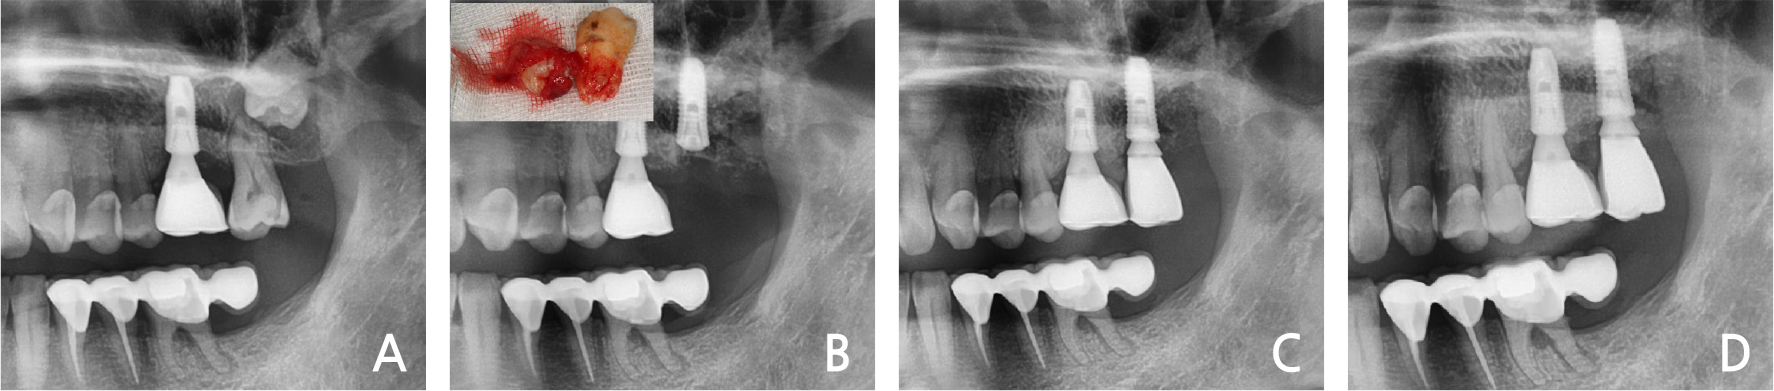

5. Case 5

A 68-year-old woman visited the dental clinic with the chief complaint of mobile left molar area. The patient exhibited severe mobility and purulent exudates in the left mandibular 2nd premolar – 2nd molar area. The radiographic view demonstrated a severe bone loss in the upper part of the mental foramen (Fig. 5A). The left mandibular 2nd premolar & 2nd molar were extracted, and immediate implant placement was performed with bone graft. The primary stability of the mandibular left 2nd premolar area was achieved by the mesio-lingual 3 mm intact bone (Fig. 5B). After one month, the dental restoration was fabricated (Fig. 5C). There have been no abnormal findings in the examination for the past 3 years (Fig. 5D).